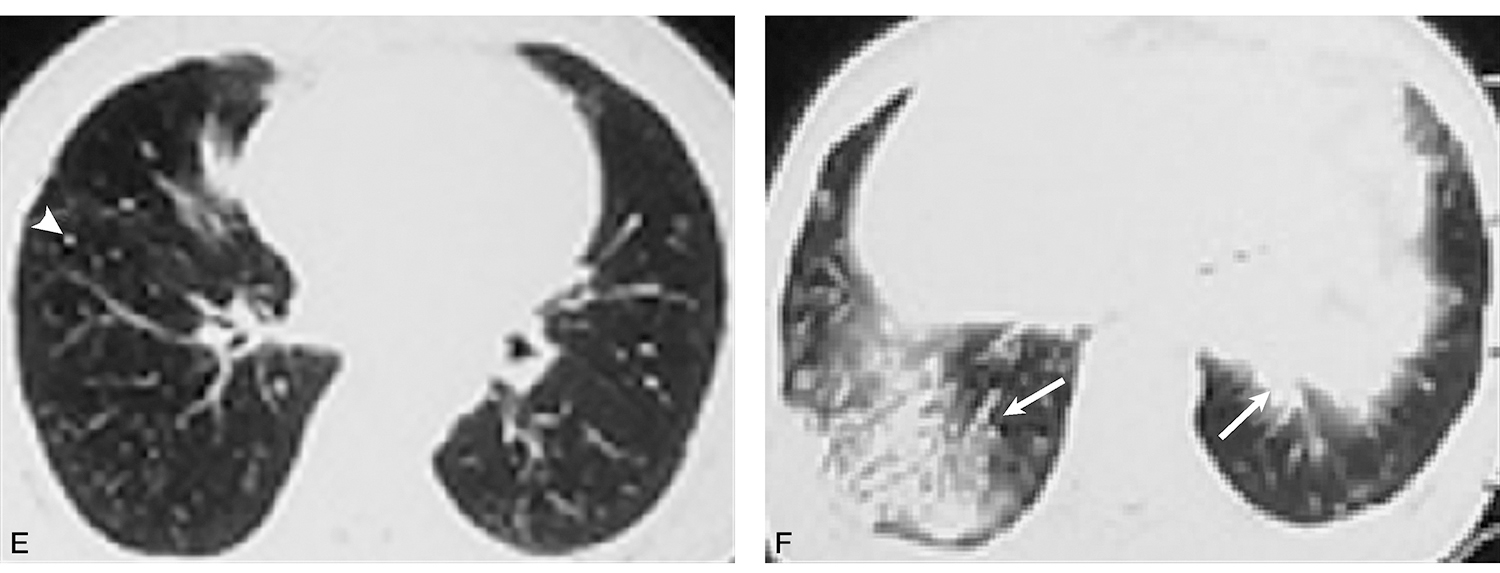

胸部增强CT(本院,2018-03-05,图3):右肺中叶条索影,支气管扩张;两肺下叶多发结节影、条索影、斑片影并牵拉性支气管扩张。

图3胸部增强CT示两肺下叶多发结节影、条索影、斑片影,并牵拉性支气管扩张